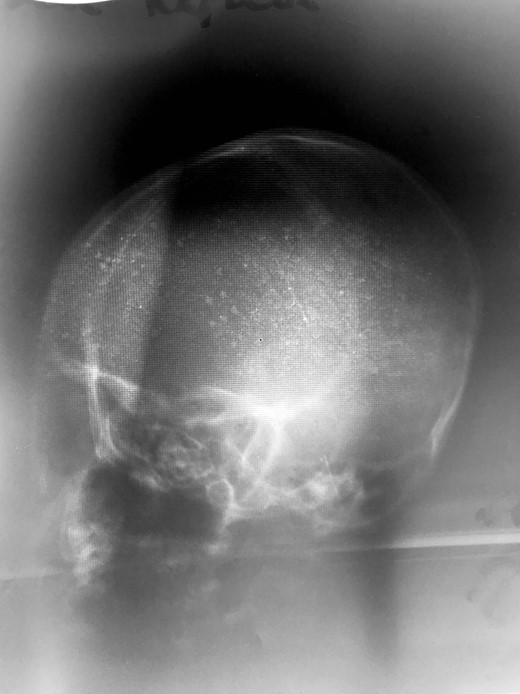

The patient’s initial work-up included a full blood count, type and cross-match for transfusion, and X-ray imaging of his head and lateral cervical spine. The X-rays were both performed at the primary medical facility. Head X-ray was of poor quality, but did not reveal any obvious injuries (Fig. 3). Cervical spine X-ray imaging was lost on transfer, and repeating the cervical spine X-ray at the tertiary hospital would have delayed operative treatment. Cross-sectional imaging was not performed, as CT scanning is not available at the tertiary hospital. His full blood count was notable for a hemoglobin of 11.3 g/dl and platelet count of 202 (x106 u/ml).

Lateral head X-ray. No other imaging modalities were available or functional at time of patient presentation.